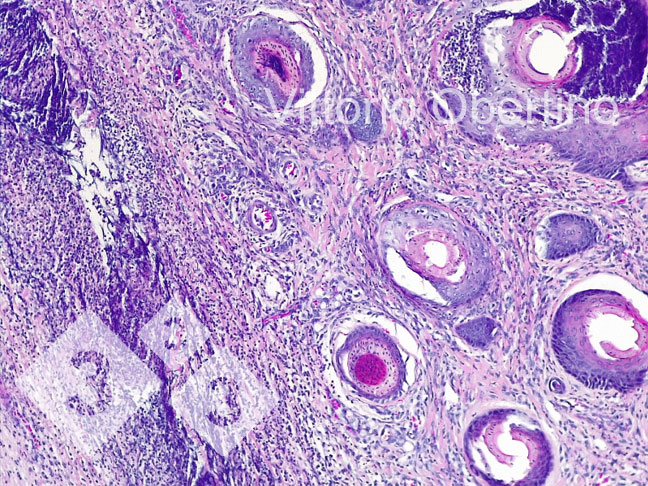

2- Campioni di tessuto sono stati inviati all’università degli studi di Torino per verificare che a livello istologico le lesioni fossero compatibili con i quadri descritti in letteratura(Kuehling et al. 2020).

- La presenza di lesioni cliniche e il quadro istologico riferibile alle stesse.